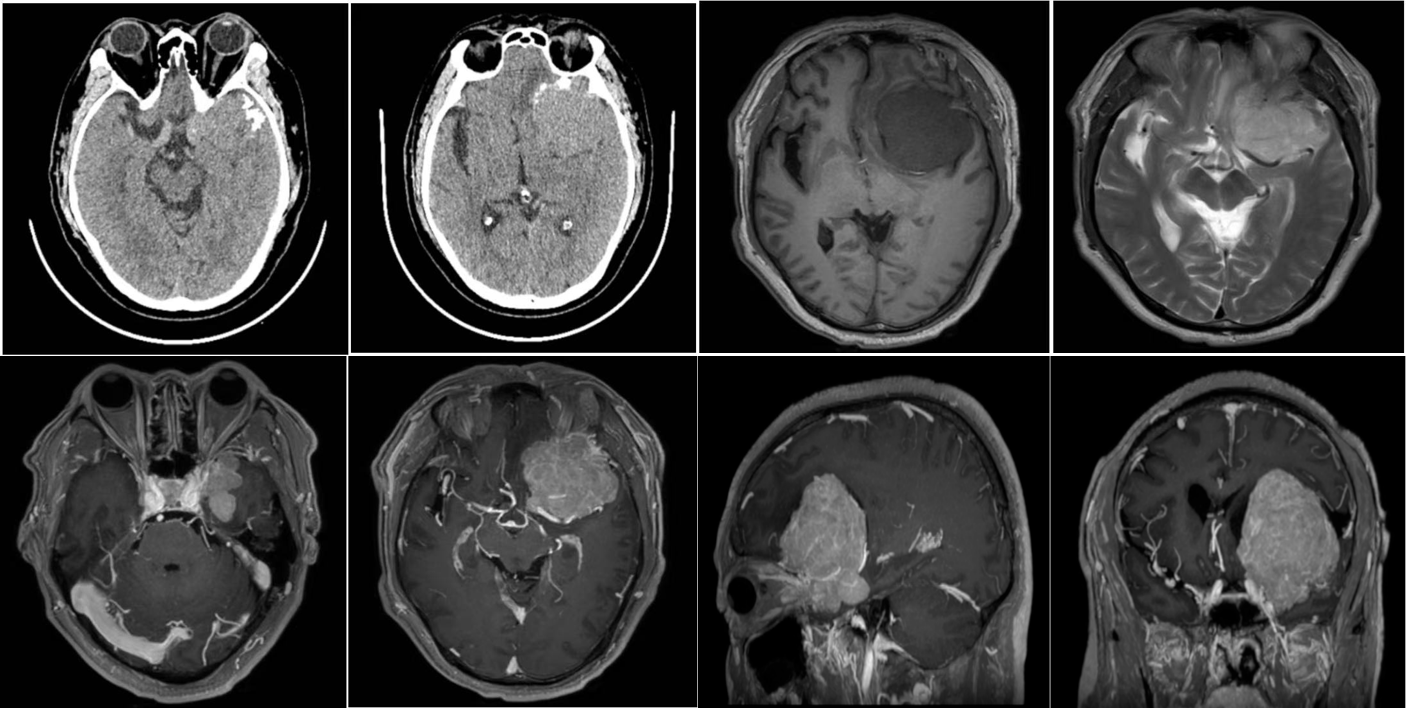

影像学表现

右侧鞍旁可见一团块分叶状软组织信号影并包埋右侧颈内动脉及大脑中动脉M1段,T1WI呈等信号、T2WI呈稍高信号,DWI呈等信号,大小约4.8X4cm,增强扫描呈明显强化,可见邻近硬脑膜强化,邻近蝶骨嵴骨质增厚,肿块周围见大片状水肿信号。中线结构向左移位。

影像学诊断

右侧鞍旁占位,考虑蝶骨嵴脑膜瘤。

病理诊断:右侧蝶骨嵴脑膜瘤(纤维上皮型)

蝶骨嵴脑膜瘤的病理类型通常为上皮型、纤维型或过渡型,其影像学表现与其他位置脑膜瘤类似,典型的CT表现为团块状或扁平状均匀地软组织密度影,MR T1WI呈等信号、T2呈稍高信号,增强后呈明显较均匀强化并可见脑膜尾征。肿瘤常累及海绵窦并包绕颈内动脉,甚至可突向鞍内。有时可见肿瘤沿视神经管或眶上裂向眼眶内生长。肿瘤邻近的骨质可见侵蚀破坏或由于长期慢性刺激可造成骨质增生硬化。